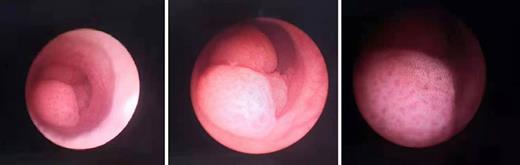

A forty-four-year-old man has come to our hospital due to hematuria for 1 week, and ultrasound showed that there were multiple calculi in the left kidney. A few days later, ureteroscopy with holmium laser lithotripsy was performed. However, during the surgery, three cauliflower-like neoplasms were found in the left proximal ureter (shown in Fig. 1). Apart from lithotripsy, we have checked that there was no neoplasm in all left renal calices through flexible ureteroscope. Besides, biopsies of the neoplasms were also taken from the ureter, and later results have shown that they were high-grade papillary urothelial carcinomas. Moreover, after the surgery, renal emission computed tomography has suggested that the patient may also suffer from CKD, while the injury of the right kidney was more severe than that of the left one. Besides, we got to know that he has taken Aristolochia for medical use without the permission of doctors, which may result in ureteral carcinoma. Because of his renal function, the patient asked for kidney-sparing therapy regardless of high-risk pathological finding. Later, segmental ureterectomy of the left side was conducted, and pathological finding of the carcinoma was the same as the first time.